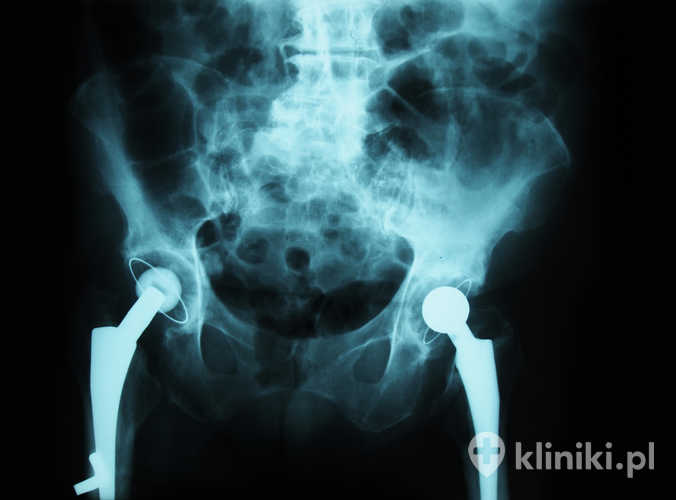

W ostatnich latach dokonał się duży postęp w protezoplastyce stawu biodrowego. Zmianie uległy prawie wszystkie elementy, począwszy od stopów metali używanych do produkcji implantów biodra, a skończywszy na materiałach służących jako powierzchnie stawowe. Te ostatnie cechują się obecnie mniejszymi współczynnikami tarcia, co zmniejsza ich zużycie w czasie.

Modyfikacje nie ominęły również samego kształtu endoprotez. Projektuje się je w taki sposób, aby pasowały idealnie do przekroju jamy szpikowej. Pozwala to na równomierne przenoszenie obciążeń i zmniejsza ryzyko osteolizy.

Dodatkowo o trwałości decyduje rodzaj pary tarciowej (np. ceramika–ceramika, ceramika–polietylen o wysokim stopniu usieciowania, metal–polietylen). Nowoczesne, wysoko usieciowane polietyleny i ceramika wykazują mniejsze zużycie niż starsze rozwiązania. Niektóre starsze konstrukcje metal–metal wiązały się z ryzykiem reakcji na drobiny metalu; obecnie stosuje się je rzadko i wyłącznie w wybranych wskazaniach. O doborze materiałów decydują m.in. wiek i aktywność pacjenta oraz jakość kości.

Oprócz wyboru właściwego implantu biodra równie ważna dla jego żywotności jest właściwa technika operacyjna. Metody endoprotezoplastyki bezcementowej stawu biodrowego przynoszą lepsze odległe wyniki, ale są zarezerwowane wyłącznie dla pacjentów z dobrą jakością tkanki kostnej.

Dla osób starszych, z nasiloną osteoporozą, rozwinięto w ostatnich latach procedury z użyciem cementu jako elementu stabilizującego trzpień i panewkę protezy. Dzięki zmianom w technologii cementowania średni czas od zabiegu do pojawienia się pierwszych ubytków związanych ze zużyciem protezy to 7 lat.

Zarówno technika cementowa, jak i bezcementowa osiągają bardzo dobre wyniki w rejestrach – wybór zależy przede wszystkim od wieku, jakości kości, budowy anatomicznej i chorób współistniejących. O powodzeniu decydują także precyzyjne osadzenie komponentów, przywrócenie prawidłowej długości i offsetu kończyny oraz dbałość o tkanki miękkie.